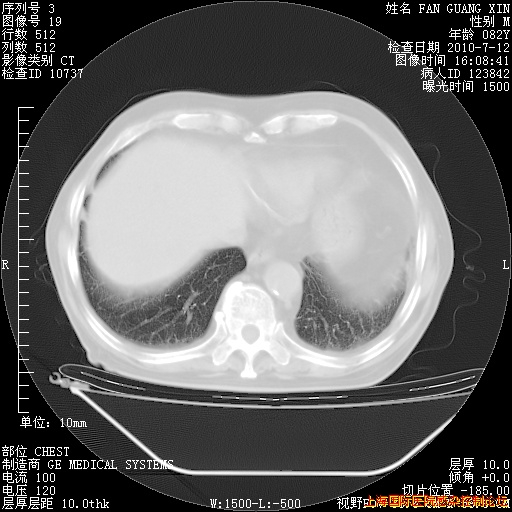

今天复查CT

今天CT

整整相隔30天的肺部CT好像有所好转啊。甲强龙减量第3天,需要观察体温。